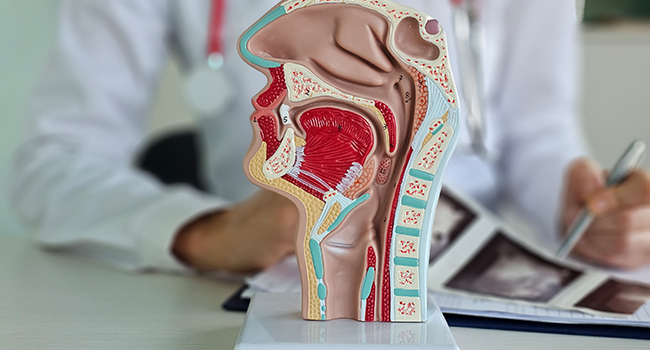

Tanı Nasıl Konulur?

Koku ve tat bozukluklarının nedenini belirlemek için KBB muayenesi yapılır ve gerekirse aşağıdaki testler uygulanır:

- Endoskopik burun muayenesi

- Koku testleri (Sniffin’ Sticks vb.)

- Tat testleri (taste strips)

- MR/BT görüntüleme (Polip, sinüs hastalığı, tümör şüphesi)

- Kan testleri (vitamin eksikliği, tiroid fonksiyonları vb.)

Bu kapsamlı değerlendirme sayesinde bozukluğun nedeni netleştirilir ve kişiye özel tedavi planlanır.